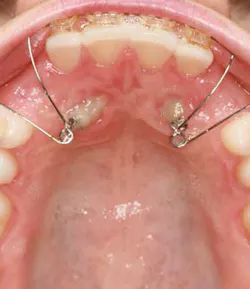

When a full permanent dentition is present (with the exception of impacted canines), the labial/palatal position of the canine will have an influence on what the provider can do. (1) Arguably, obtaining a CBCT is considered mandatory and will allow for a more inclusive treatment plan creation. If angulation is favorable, then consideration to remove the primary canine and wait six months to see if there is movement of the permanent canine is an option. If extraction of the canine(s) is needed, then a premolar substitution, which is dependent on occlusion, can be used in the space. An implant can also be an appropriate alternative. When pulling a canine into the occlusal arch, there is risk involved. Trauma to adjacent teeth (root resorption) and ankylosis are some of the most common complications.The patient was put in full orthodontics and referred to a surgeon for extraction of the primary canines, exposure, and placement of retention on the impacted canines to pull them directly down from their current position.

A ballista appliance was used to prevent a facial pull of the canines in order to avoid and prevent resorption of the roots of the lateral incisors. As movement progressed over the course of the next year, eruption of the canines was considered a success. Once in position, they will be pulled facially into occlusion.